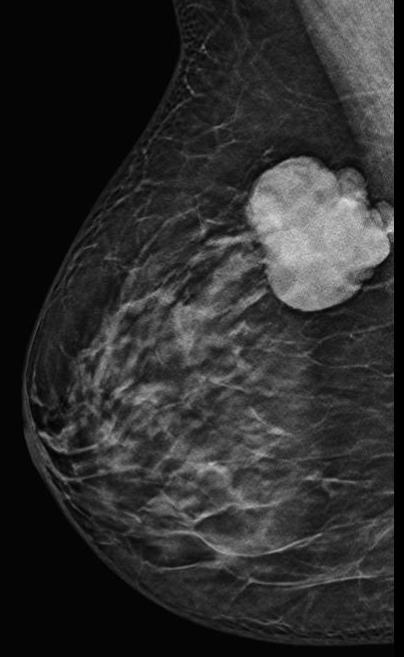

Bilateral digital mammography with tomosynthesis and ultrasonography was done. Mammography revealed a high-density irregular mass with multilobulated margins in the upper and outer quadrant of the left breast. The mass was located eccentric to the nipple. No associated calcifications were seen.No axillary lymphadenopathy. Ultrasonography revealed a hypoechoic irregular mass with multilobulated margins at 2 o clock position in the left breast. Color doppler revealed minimal peripheral vascularity. Arfi elastography revealed the mass to be hard. A BI-RADS assessment category of 4C was given with a recommendation for a core needle biopsy. Histopathology Invasive ductal carcinoma .IHC -ER 95 %,PR-95% ,HER 2 -Negative and KI -67-20%. PET CT revealed an FDG avid lesion in the upper outer quadrant of the left breast with no axillary or distant metastases.